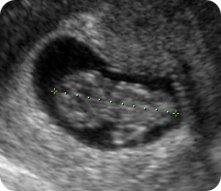

Ултразвучниот преглед во оваа фаза од бременоста е карактеристичeн поради тоа што ембрионот, иако е многумал, веќе наликува на бебе, а може да се забележи и негово движење. Особена радост за идните родители е прикажувањето на нивното бебе по прв пат, неговите движења и приказот на неговото срце кое се гледа на мониторот. Прегледот опфаќа и испитување со доплер, при што идните родители може да го слушнат срцето на бебето. Сите овие моменти се значајни за идната мајка и нејзиниот партнер. Присуството на обајцата родители помага во формирањето на една посилна емотивна врска помеѓу партнерите која делува позитивно на мајката, на текот на бременоста, на породувањето и понатаму при воспитувањето на детето кое сега е големо само неколку сантиметри.

Поточно, на овој преглед повторно се мери должината на ембрионот (CRL) која изнесува околу 25 mm.